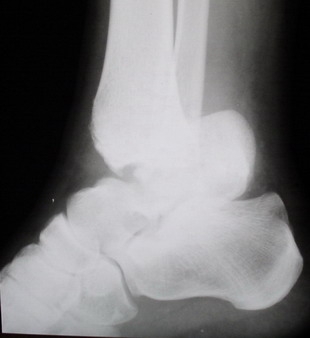

Глубокоуважаемые коллеги! Просим совета в лечении пациента с последствиями тяжелой сочетанной травмы. Пациент С., 41 года, по профессии бизнесмен, в сентябре 2005 г. пострадал в дорожно-транспортном происшествии (упал с мотоцикла). Диагноз: ЗЧМТ, ушиб головного мозга тяжелой степени. Открытый переломо-вывих левой таранной кости. Закрытые переломы лонной и седалищной костей слева. Был доставлен в НИИСП им. Н.В. Склифосовского. При ПХО раны выявлен открытый перелом левой таранной кости (III тип по Hawkins) с утратой вывихнутого тела таранной кости. Выполнена ПХО, фиксация голени и стопы стержневым аппаратом. Рана зажила без осложнений. Аппарат демонтирован через 1,5 месяца. В настоящее время больной предъявляет жалобы на боль в голеностопном суставе при нагрузке. Передвигается с опорой на костыли с дозированной нагрузкой на левую стопу.Голень и стопа фиксированы циркулярной пластиковой повязкой. Сохраняются остаточные явления ЧМТ (в виде сниженной критики к своему состоянию и определенной недисциплинированности в выполнении врачебных рекомендаций) Рентгенограммы – рис. 1, 2 (просим извинения за низкое качество рентгенограмм), схема – рис. 3. В качестве варианта хирургического лечения мы считаем возможным выполнить следующее вмешательство: артродез большеберцовой и пяточной костей в сочетании с артродезом переднего края большеберцовой кости и головки таранной кости с фиксацией спонгиозными винтами. Считаем выполнение артродеза переднего края большеберцовой кости и элементов I луча стопы необходимым для максимального восстановления опороспособности конечности. Однако выполнение операции в указанном объеме привело бы к относительному укорочению внутреннего свода стопы. Мы видим два пути решения данной проблемы: Вариант 1. Применение костного трансплантата (свободного или на сосудистой ножке) для замещения дефекта головки таранной кости и сохранения геометрии внутреннего свода стопы (рис 4). Преимущество: относительная простота операции. Недостаток: высокий риск замедленной консолидации или лизиса трансплантата. Вариант 2. Резекция участка пяточной кости с последующим остеосинтезом винтами для укорочения наружного свода стопы (рис 5, 6). Преимущества: сохранение собственного кровоснабжения всех синтезируемых участков костей. Недостатки: дополнительная травматизация, усугубление деформации стопы в виде нарушения наружного свода. Будем признательны за ваши предложения, включая возможные альтернативные варианты лечения.Заранее благодарны за добрые советы и поддержку. А. Федосов, О. Диденко, П. Иванов. Отделение множественной и сочетанной травмы НИИСП им. Н.В. Склифосовского, г. Москва.

Ваша дискуссия заставила перелистать свои наблюдения.

Среди повреждений таранной кости (Hawkins III-IV) с одновременной травмой лодыжек встретилось следующее (см. вложение). Пациент упал в колодец на глубину 10 метров (Х.2002 г.), госпитализирован с диагнозом: з/перелом шейки правой таранной кости (Hawkins IV) с переломовывихом тела назад и кнутри, закрытый перелом внутренней лодыжки и переднего края большеберцовой кости. Оперирован в первые 12 часов после травмы, выполнена открытая репозиция таранной кости, внутренним и передне-внутренними доступами, остеосинтез переломов шейки и тела губчатыми винтами, для реваскуляризации тела таранной кости первичный компрессионный над- и подтаранный артродез. Синтез внутренней лодыжки губчатым винтом. Удаление винтов через 1 год,2 мес. Получен анкилоз указанных суставов с сохранением длины конечности, полная реваскуляризация таранной кости, о чем говорит сращение ее переломов, отсутствие отеков и

цианоза стопы и голени. Компенсаторная подвижность переднего и среднего отделов стопы около 15-20 градусов за счет поперечного (Шопара) сустава стопы. Считаю оправданной подобную тактику, не смотря на угрожаемый прогноз (100% асептический некроз) по классифицкации Hawkins.